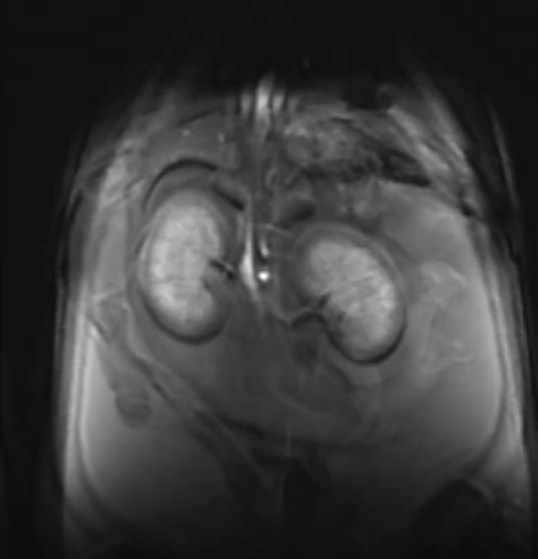

The MRI system is equipped with a 7.0 T, 310 mm diameter horizontal-bore superconducting magnet interfaced with General Electric 's Signa HDx platform. The system provides high quality and robust pre-clinical MRI research capabilities with a variety of imaging contrasts and quantitative assessments. PCIC provides a service to address a broad range of researchers' needs, from live animal imaging to specimen investigations and contrast agent characterization to material and plant research.

The imaging is performed using a strong 300 mT/m (30 Gauss/cm) gradient system (210 mm inner diameter) equipped with 2nd-order shim capability. A wide range of radio frequency probes (coils) are available, ranging from animal full body volume coils to dedicated, actively decoupled receive coils for mouse and rat brain. Systems for physiological monitoring and animal handling are also available. The MRI spectrometer is equipped with X-nuclei capabilities.

Examples of images acquired by our 7T MRI

MRI images of rat spine, brain tumor, fat imaging and mouse in-utero